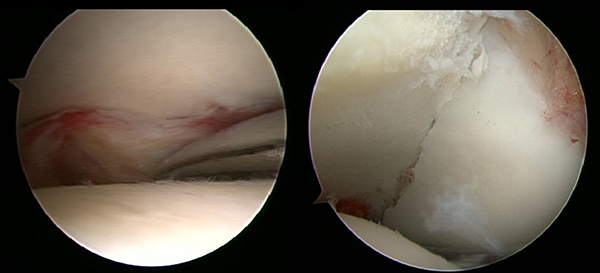

Ein aktuelles systematisches Review zur arthroskopisch-assistierten Frakturversorgung (AORIF) am Sprunggelenk identifizierte bei 495 von 782 Patienten (63,3%) chondrale Verletzungen 54. Weder durch die klinische Untersuchung noch mit konventionellen Röntgenaufnahmen oder mittels CT-Bildgebung lassen sich diese Verletzungen zuverlässig diagnostizieren. Aus diesem Grund rückt die arthroskopisch-assistierte Frakturversorgung am oberen Sprunggelenk zunehmend in den Fokus. Die Arthroskopie ermöglicht im Rahmen der Frakturversorgung sowohl die Kontrolle der Reposition als auch die Beurteilung und Therapie von intraartikulären Pathologien. Während sich die arthroskopisch-unterstützte Versorgung einiger Frakturen bereits etabliert hat (z.B. proximale Tibiafraktur) gehört der Einsatz der Arthroskopie bei der Frakturversorgung des oberen Sprunggelenks in den allermeisten Kliniken noch nicht zum Versorgungsalltag 155 Im Gegenteil, in einer aktuellen amerikanischen Datenbankanalyse des United Healthcare Orthopedic Datasets wurden zwischen 2007 und 2011 insgesamt 32 307 Patienten identifiziert, die mittels ORIF an einer Sprunggelenksfraktur versorgt wurden. In weniger als einem Prozent erfolgte eine arthroskopisch-assistierte Versorgung 55. Dem gegenüber stehen arthroskopische Studien der vergangenen Jahre, die zeigen konnten, wie häufig es zu intraartikulären Verletzungen bei Sprunggelenksfrakturen kommt. Das Risiko für diese intraartikulären Begleitverletzungen nimmt mit der Komplexität der Fraktur zu 5657. Es liegt also nahe, dass bei komplexeren Frakturen die Durchführung einer Arthroskopie im Rahmen der Frakturversorgung einen positiven Effekt auf das Behandlungsergebnis hat. Aus Sicht der Autoren sollte es Ziel für die Zukunft sein, die Frakturtypen zu identifizieren, die von einer arthroskopisch-assistierten Frakturversorgung profitieren. Die diagnostische Arthroskopie mit dem Ziel der gleichzeitigen arthroskopischen Therapie ist in der aktuellen S2-Leitlinie bereits eine Level-1b-Empfehlung. In den Abbildungen 20 – 30 ist schrittweise unser Vorgehen zur arthroskopisch assistierten Versorgung einer Trimalleolarfraktur dargestellt.